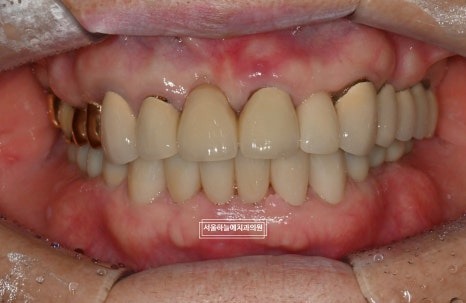

최종적으로 위아래 앞니

아래 양쪽 어금니 임플란트 보철까지

모두 안정적으로 마무리되었습니다.

처음 내원 당시와 비교하면

교합, 기능, 심미 모두에서 큰 변화가 있었고

무엇보다 환자분께서

편하게 식사하실 수 있게 되었다는 점이

가장 의미 있었습니다.